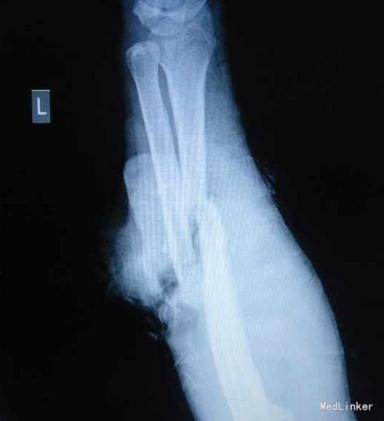

患者36岁,因“电锯锯致左前臂疼痛出血伴畸形1小时”入院

左前臂中段背侧见U形皮瓣,长约16厘米,蒂长约8厘米,蒂宽约5厘米,翻向远侧;创面轻度污染,伸肌群断裂,尺桡骨骨折端外露,有搏动性出血。1-5指背伸障碍,4、5指感觉减退,桡动脉搏动存,尺动脉搏动未触及。 X线:左尺桡骨中段粉碎性骨折,断端成角错位。